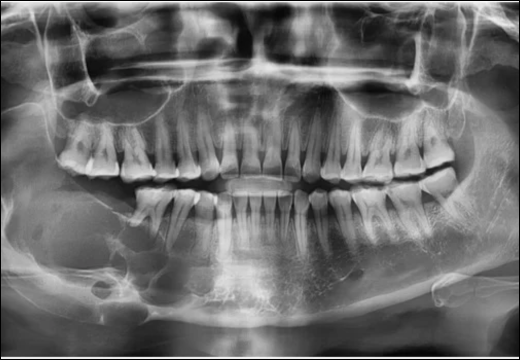

- Orthopantomography reveals multilocular “soap-bubble” radiolucencies with scalloped borders, often encompassing impacted third molars